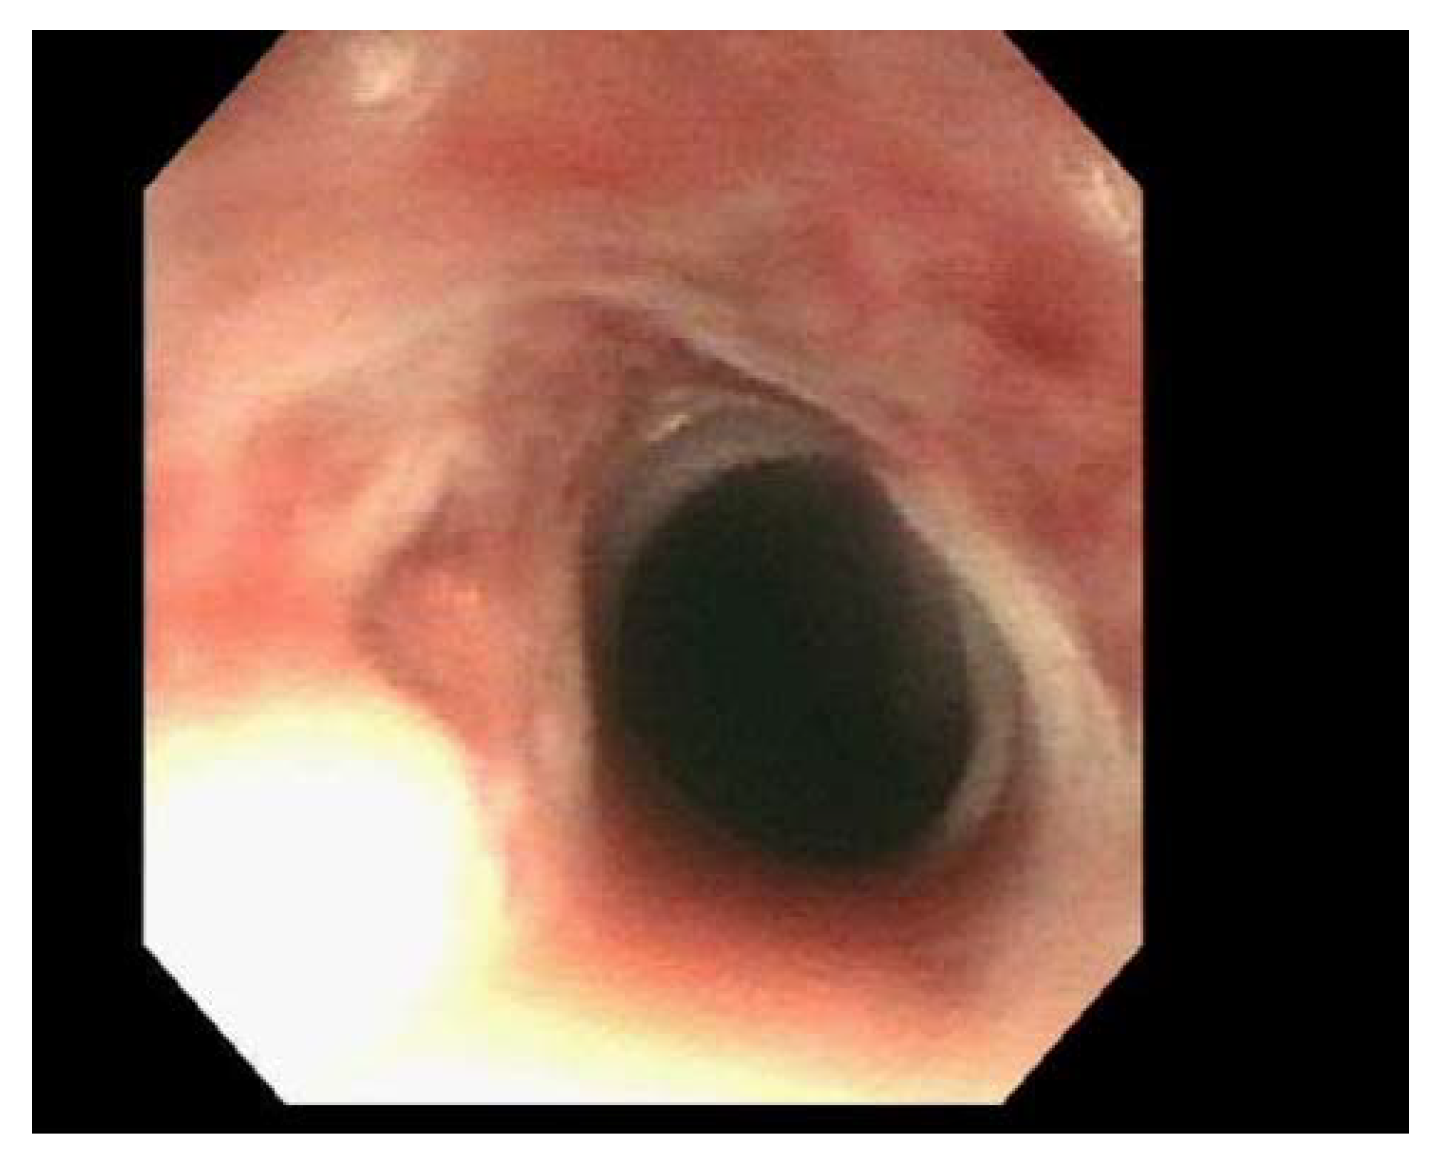

| Patient 1 | Single benign appearing intrinsic stenosis located 15 mm from the UES dilated with a TTS balloon dilator to 20 mm, gastric mucosal atrophy |

| Patient 2 | Web/stenosis at the cricopharyngeus unable to pass with neonatal scope due to resistance, guideware placed under fluoroscopic guidance and dilation performed with Savary dilator to 8 mm |

| Patient 3 | Two benign appearing intrinsic stenoses were found at the circopharyngeus at 15 cm and 20 cm from the incisors that could not be traversed with the neonatal scope, dilation performed with Savary dilators to 11 mm |